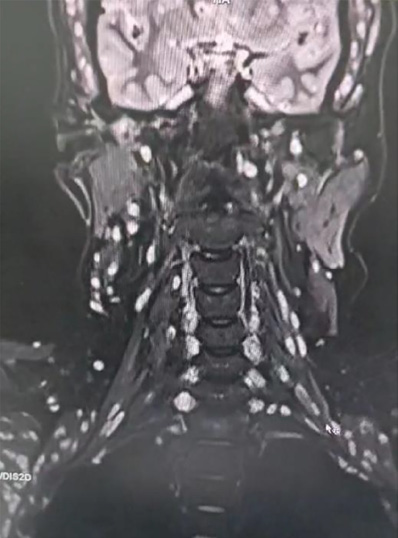

In addition, multiple cystic lesions were observed within the extraocular, facial, and tongue muscles, each containing an eccentric scolex, consistent with disseminated myocysticercosis (Figures 2 and 3). These lesions exhibited hyperintense signals on T2-weighted and hypointense signals on T1-weighted sequences, confirming their parasitic nature.

Spinal MRI revealed reversal of cervical lordosis with diffuse disc bulges at levels C3/4, C4/5, C5/6, and C6/7, causing mild anterior thecal-sac indentation but without evidence of cord compression or myelomalacia (Figures 4–7) [5]. The lumbar spine showed disc desiccation with a diffuse bulge at L4–L5, indenting the thecal sac yet preserving normal vertebral body height and marrow signal intensity. No paravertebral abscess, vertebral destruction, or compressive myelopathy was noted [6].

Explanation: Muscular involvement was detected through MRI, which revealed multiple cystic lesions within the extraocular, facial, and tongue muscles. The presence of an eccentric scolex inside these lesions confirmed that they were parasitic in origin, indicating disseminated myocysticercosis, which is an uncommon but clinically relevant finding.